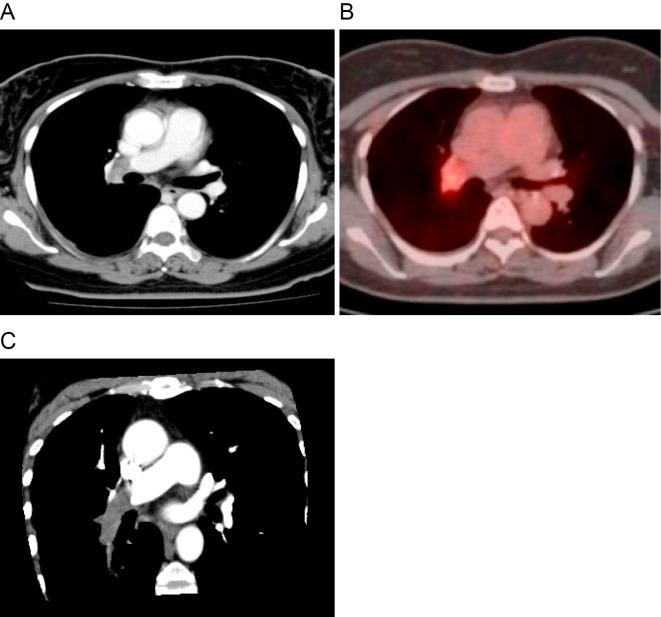

Pulmonary artery sarcoma is highly malignant and easily metastasizes to the systemic organs. Both the introduction of novel diagnostic procedures and the development of new treatment modalities are required to achieve long-term survival. Several studies have shown that platelet-derived growth factor receptor α (PDGFRα) gene amplification is frequently observed in pulmonary artery sarcoma. PDGFRα is known to be involved in cell proliferation in certain malignancies. PDGFRα may become a potential biological marker in pulmonary artery sarcoma. We report a case in which a diagnosis of pulmonary artery sarcoma overexpressing PDGFRα was made using endovascular catheter biopsy following positron emission tomography with integrated computed tomography (PET/CT) scans.

肺动脉肉瘤恶性程度高,易转移至全身各器官。为实现长期生存,既需要引入新的诊断方法,也需要开发新的治疗方式。多项研究表明,肺动脉肉瘤中经常观察到血小板衍生生长因子受体α(PDGFRα)基因扩增。已知PDGFRα参与某些恶性肿瘤的细胞增殖。PDGFRα可能成为肺动脉肉瘤潜在的生物学标志物。我们报告一例病例,该病例通过正电子发射断层扫描与计算机断层扫描(PET/CT)联合扫描后,采用血管内导管活检确诊为过表达PDGFRα的肺动脉肉瘤。